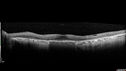

Concentric Geographic Atrophy

76 year old man Gradual vision loss

20/32 OD; 20/40 OS

No medicines, Non-smoker

Working and Driving